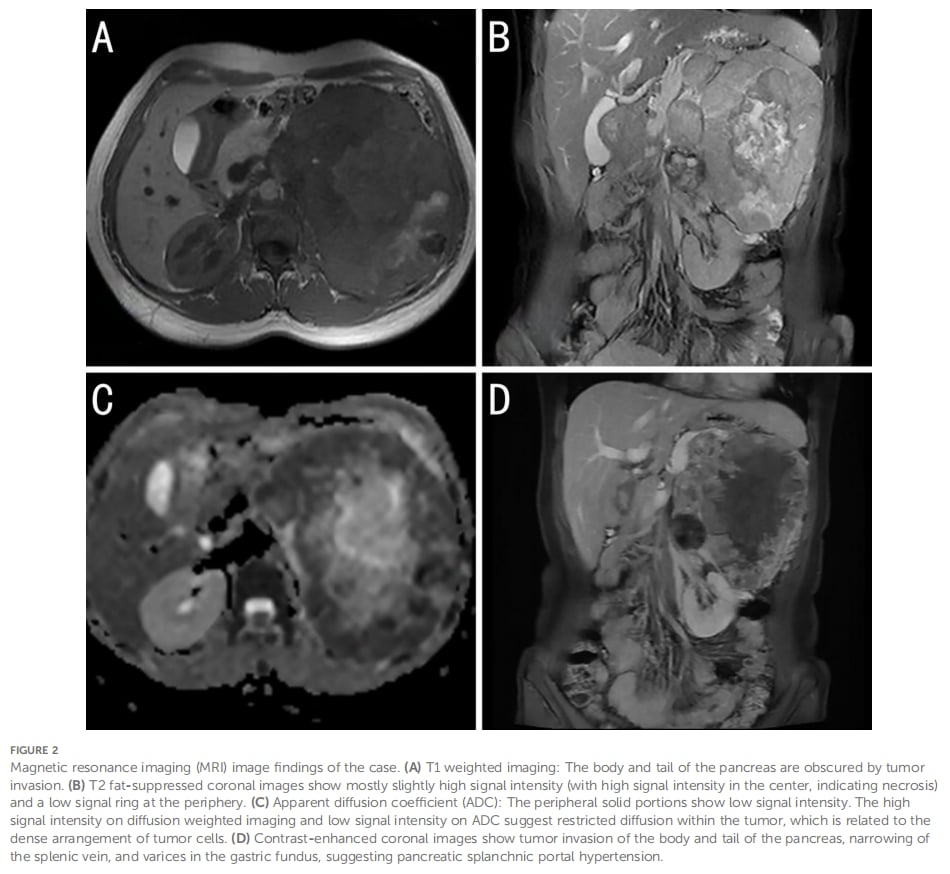

MRI进一步提示病灶信号混杂、局部扩散受限、强化明显不均,同时周围可见多发扩张静脉。这些表现支持恶性肿瘤可能,但依然不能仅凭影像锁定病理类型。

MRI可提示病灶恶性倾向,但对罕见肾癌亚型的定性能力有限,最终仍需病理与分子检测。